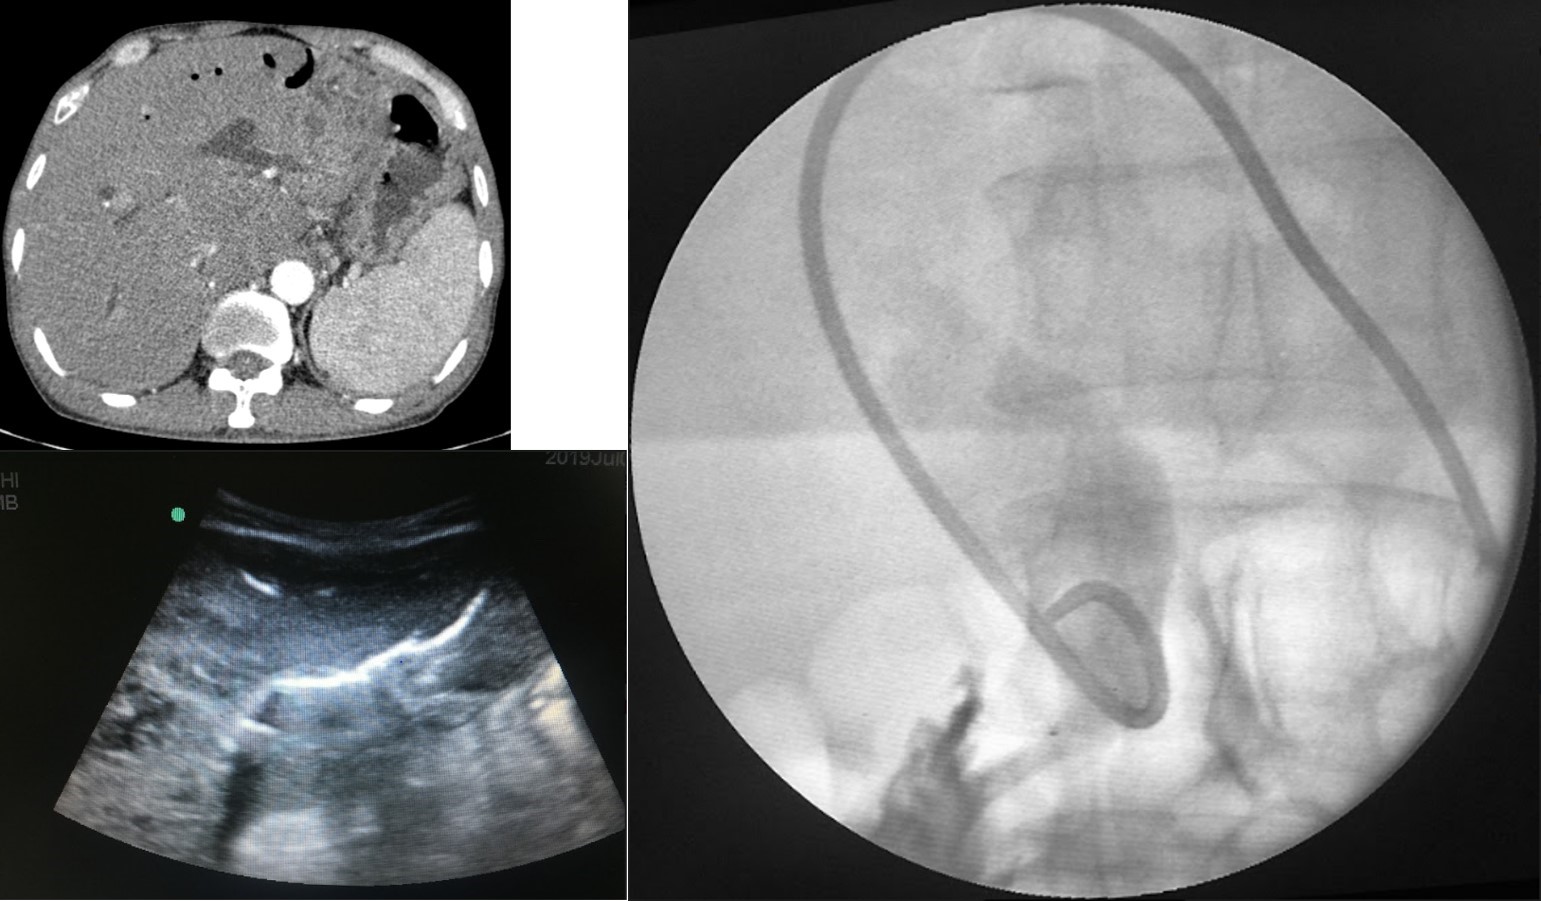

U đường mật rốn gan (Klatskin type IV) xâm lấn đường mật 2 bên. PTBD hai bên (chữ Y) giảm áp đường mật, cải thiện triệu chứng. Bệnh nhân được hóa trị sau đó.